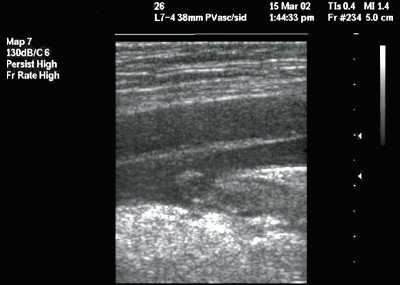

Статическая методика: контрольное УЗИ с визуализацией интересуемых сосудов выполнялось непосредственно перед пункцией центральных вен, разметка на коже наносилась до стерилизации операционного поля (рис.1). УЗИ проводилось в двух взаимно перпендикулярных плоскостях в поперечном и сагиттальном (продольном) сечении между ножками грудино-ключично-сосцевидной мышцы при исследовании внутренней яремной вены (рис. 2, 3) и в паховой складке при исследовании бедренной вены. С помощью предварительного УЗИ определяли глубину расположения вены от поверхности кожи, непосредственно ход венозного ствола, диаметр вены, диаметр артерии, взаимное расположение вены и артерии, степень сокращения (спадения) внутренней яремной вены на вдохе при наличии гиповолемического состояния.

Рис. 3. Нормальное расположение и размеры внутренней яремной вены и сонной артерии при исследовании в продольном сечении (сонная артерия находится глубже внутренней яремной вены).